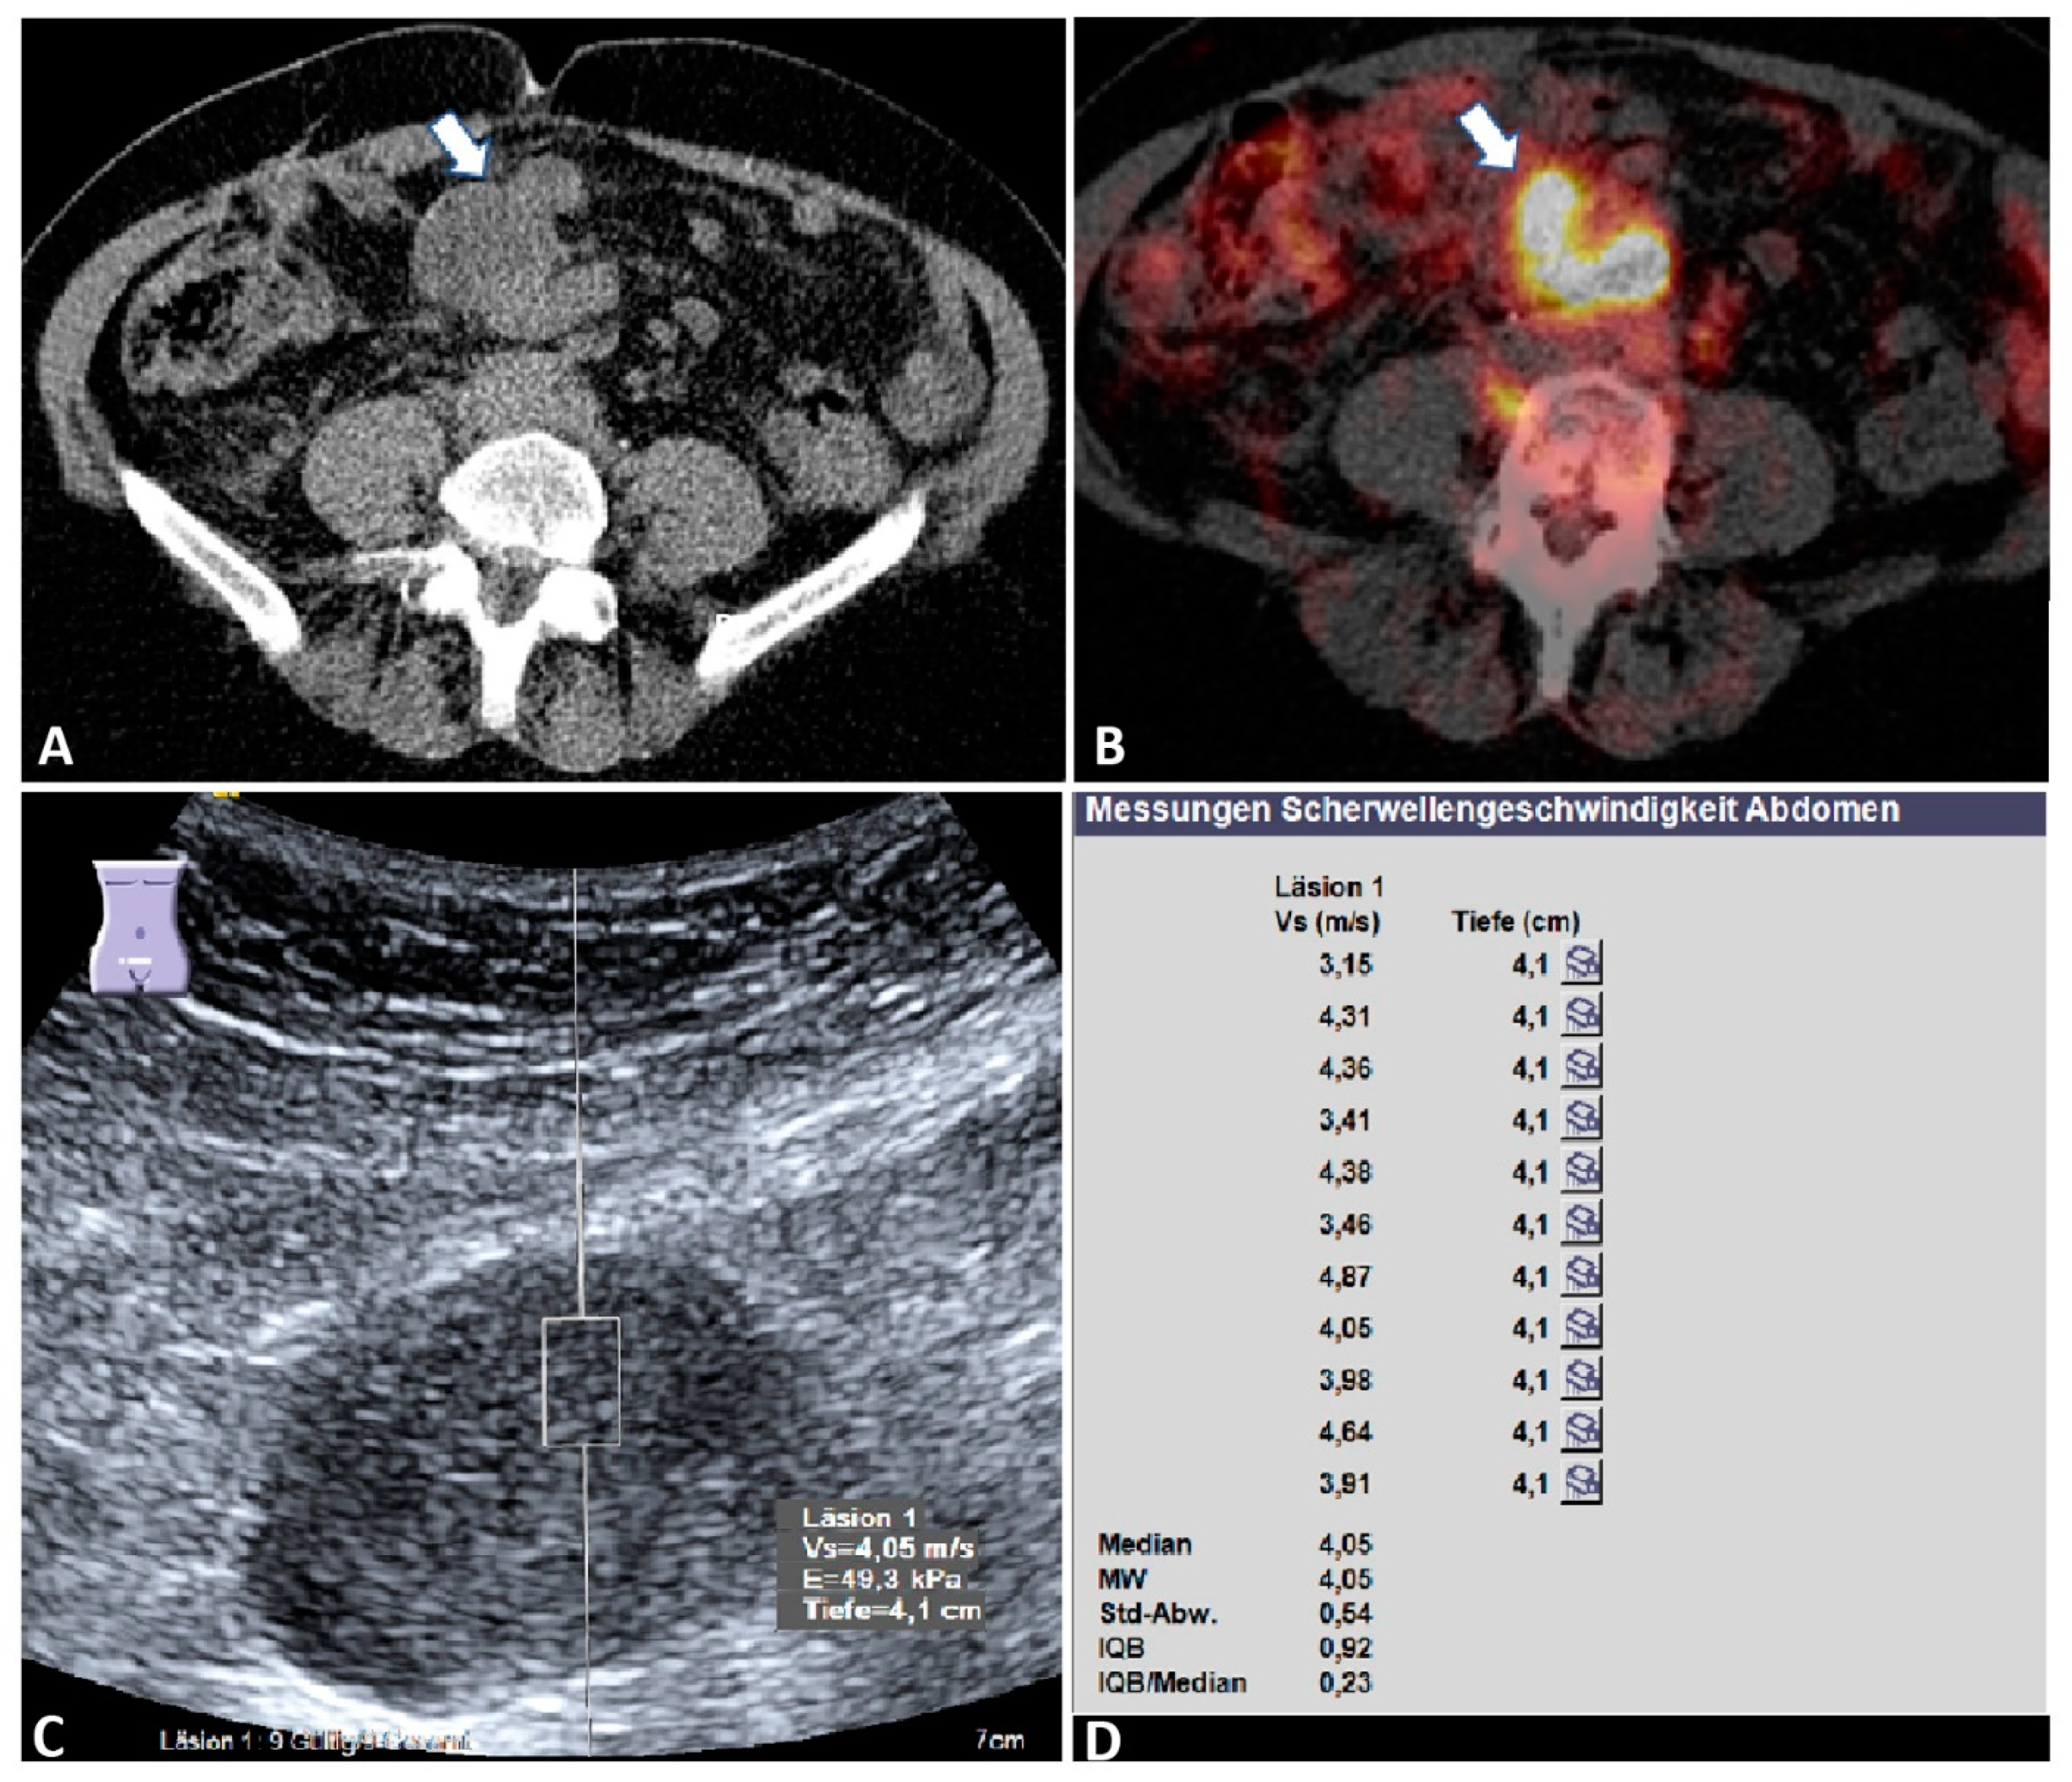

| mMMs | 32 | 2.76 ± 1.01 | 0.77 | 4.22 | 4.25 ± 0.80 |

| Hematological | 15 | 2.73 ± 1.03 | 0.77 | 4.18 | 4.47 ± 0.78 |

| Present study | 69 | ARFI elastography | Mean velocity > 2.05 m/s | 75 | 70 | 69 | 77 | <0.001 |